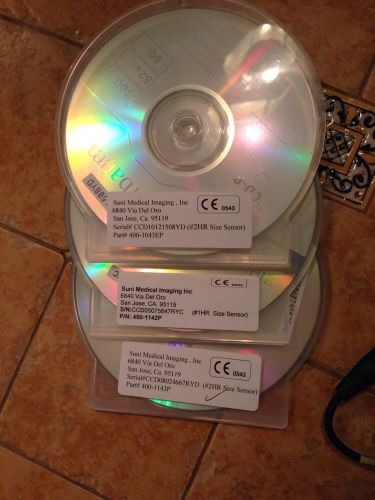

Suni Medical Imaging Digital Xray Senors And Usb Interface Boxes